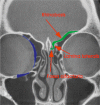

Fractures of the midface pose a serious medical problem as for their complexity, frequency and their socio-economic impact. Interdisciplinary approaches and up-to-date diagnostic and surgical techniques provide favorable results in the majority of cases though. Traffic accidents are the leading cause and male adults in their thirties are affected most often. Treatment algorithms for nasal bone fractures, maxillary and zygomatic fractures are widely agreed upon whereas trauma to the frontal sinus and the orbital apex are matter of current debate. Advances in endoscopic surgery and limitations of evidence based gain of knowledge are matters that are focused on in the corresponding chapter. As for the fractures of the frontal sinus a strong tendency towards minimized approaches can be seen. Obliteration and cranialization seem to decrease in numbers. Some critical remarks in terms of high dose methylprednisolone therapy for traumatic optic nerve injury seem to be appropriate. Intraoperative cone beam radiographs and preshaped titanium mesh implants for orbital reconstruction are new techniques and essential aspects in midface traumatology. Fractures of the anterior skull base with cerebrospinal fluid leaks show very promising results in endonasal endoscopic repair.